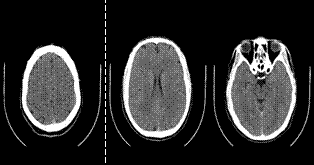

Como parte del procedimiento médico, J fue enviado al hospital de urgencia para realizarle una Tomografía Axial Computarizada de Cráneo Simple (Figura 3), que arrojó que las imágenes estaban dentro de los límites normales ya que el 4to ventrículo es central, el mesencéfalo tiene morfología y densidad normal y se demuestra el tejido cerebral con adecuada diferenciación de la sustancia gris-blanca, presenta densidad homogénea, así como amplitud normal de surcos, cisuras y cisternas.